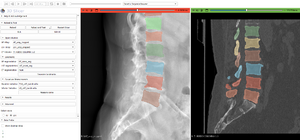

||[[Image:SpineCurveCorrection.png|thumb|left| [https://projectweek.na-mic.org/PW42_2025_GranCanaria/Projects/SimulationOfSpineCurveCorrectionThrough3DReconstructionTechniquesAndParameterMeasurement/ Simulation of Spine Curve Correction Through 3D Reconstruction Techniques and Parameter Measurement]]]

2025 January: Project Event 42

The 42th Project Event was held January 27-31, 2025, Las Palmas, Gran Canaria, Spain. More...